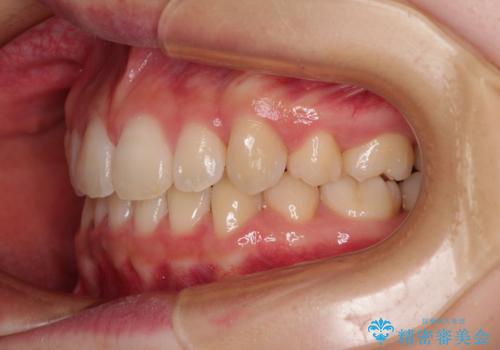

- 口元の閉じにくさを気にして来院された患者様です。

上下ともに歯列が前方に突出していたため、上下左右の第一小臼歯4本を抜去し、ワイヤー装置による矯正治療を行うこととしました。

上下左右4本抜歯する場合には、通常2年から2年半ほどの期間を要しますが、舌のトレーニングをしっかりと行っていただいたことで、1年9ヶ月で終了することができました。